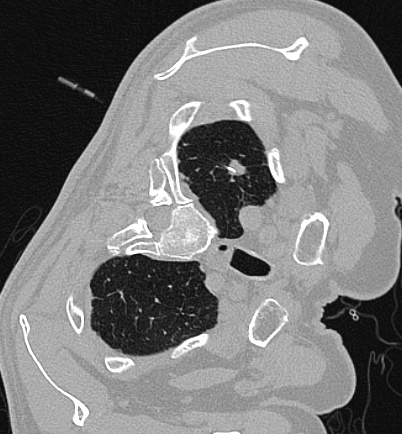

1. 影像观察“以貌取结”

大小:

结节越大,恶性风险越高。≤5mm的微小结节大多良性。

长相:

边缘光滑的常为良性;边缘有“毛刺”、分叶或胸膜牵拉的需警惕。

质地:

纯磨玻璃结节多为良性或极早期癌变;混合型磨玻璃结节若实性成分增多,风险上升。

纯磨玻璃肺结节

混合性肺磨玻璃结节

实性肺结节